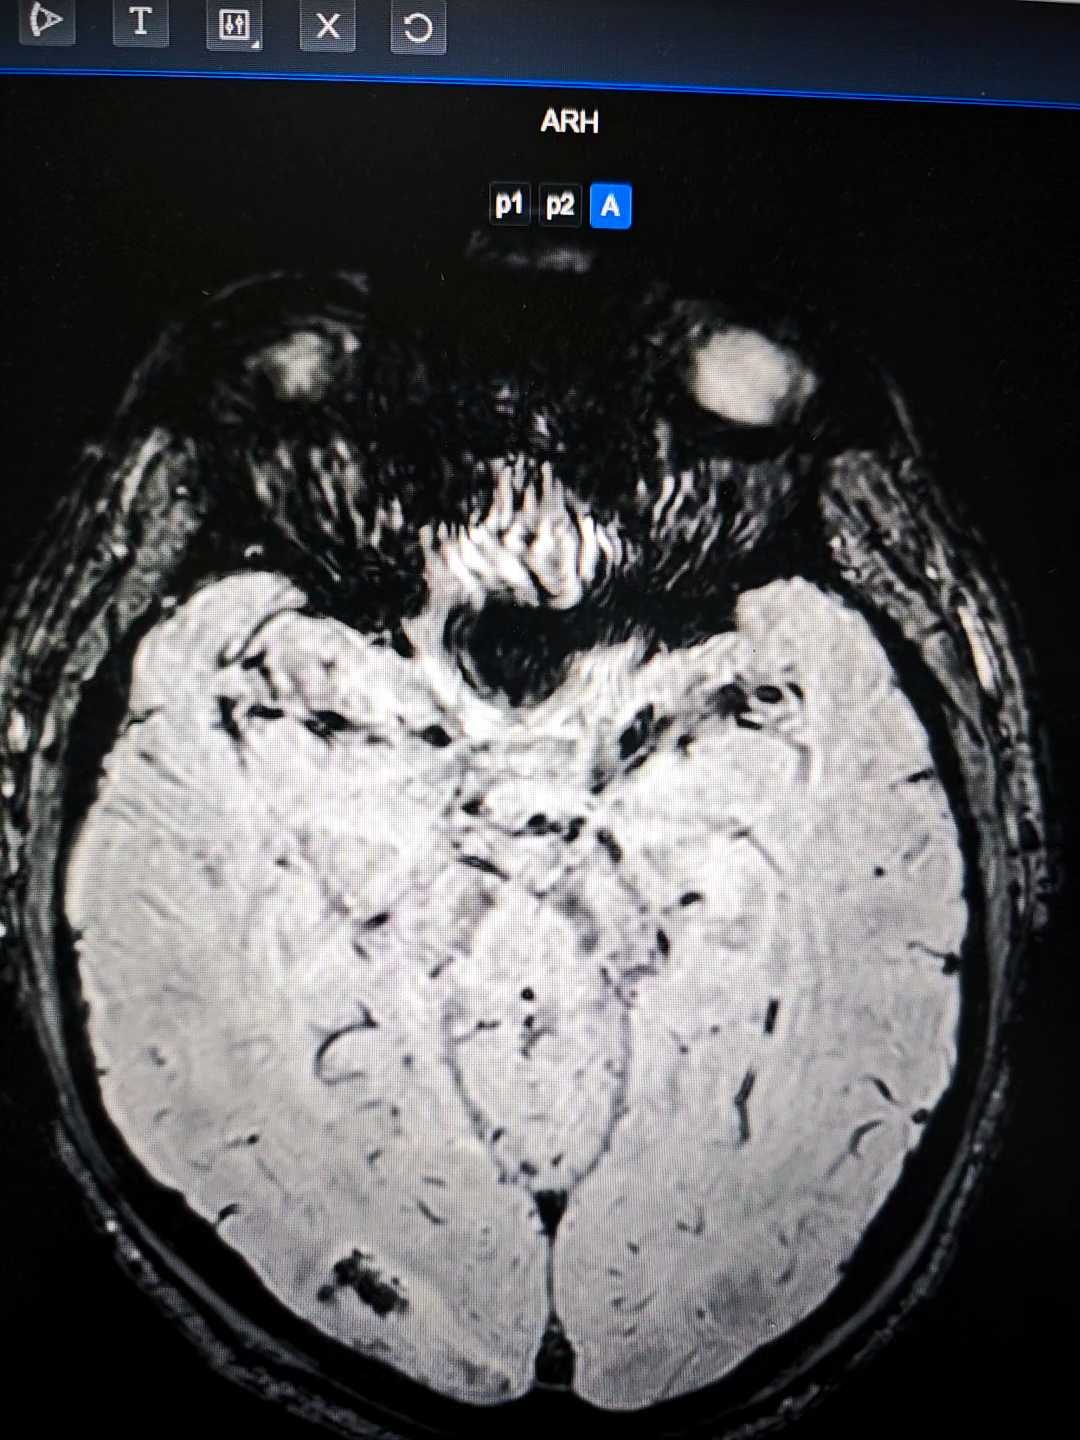

病例疑难:颅内多发病变

患者57岁,2天前因左上肢远端突发乏力体检发现颅内多发病变,目前患者无特殊不适。